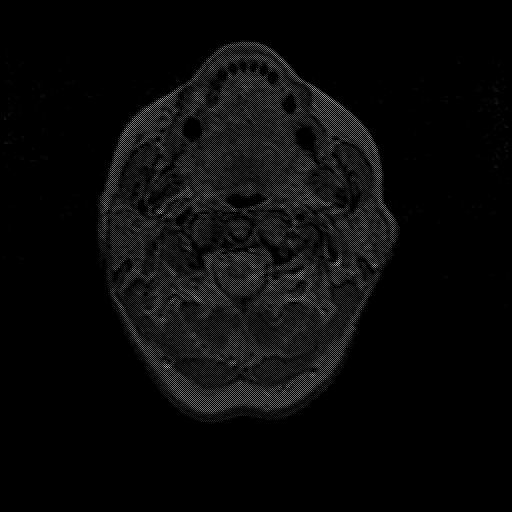

overlay : Slice 1

Slice 1

MRCBFCBF with

T1PDT2T1PDT2